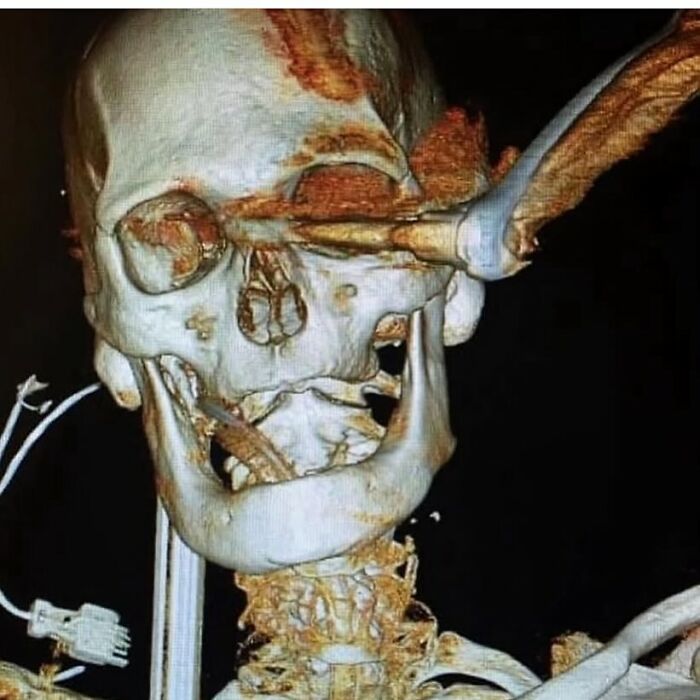

Internal Decapitation